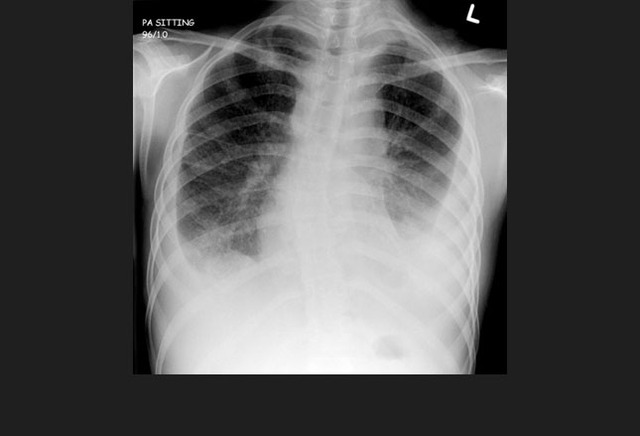

图2. 无数的肺部小结节,与粟粒型肺结核表现一致

初次感染结核常为隐匿性经过,少数患者可能会有明显的血液播散,导致粟粒型肺结核。